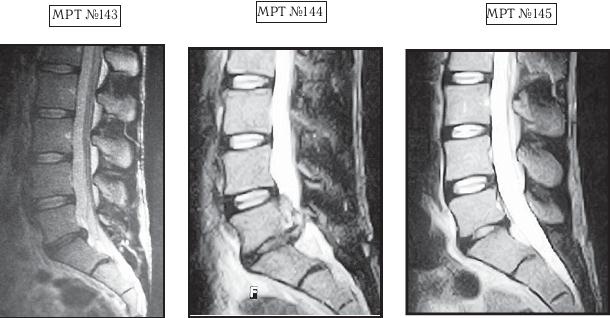

На МРТ №143 наблюдается состояние поясничного отдела позвоночника данного пациента до оперативного вмешательства: незначительных размеров грыжа межпозвонкового диска в сегменте LV-SI. Была проведена хирургическая операция межпозвонкового диска в сегменте LV-SI с целью профилактики возможных осложнений и дальнейшего прогрессирования грыжи.

На МРТ №144 наблюдается состояние поясничного отдела позвоночника того же пациента после хирургического вмешательства: рецидив грыжи (но уже со значительным секвестром) межпозвонкового диска в сегменте LV-SI, стеноз позвоночного канала и, естественно, соответствующие осложнения, вызванные такой ситуацией (во избежание которых собственно и была проведена операция).

На МРТ №145 наблюдается состояние поясничного отдела позвоночника того же пациента после одного курса лечения методом вертеброревитологии: отсутствие секвестрированной грыжи, стеноза позвоночного канала.